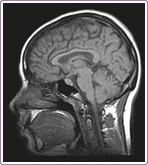

En la Resonancia Magnética las imágenes se realizan mediante cortes en tres planos: axial, coronal y sagital, sin necesidad de que el paciente cambie su posición. Las resonancias magnéticas atraviesan los huesos, por ello se ven muy bien los tejidos blandos.